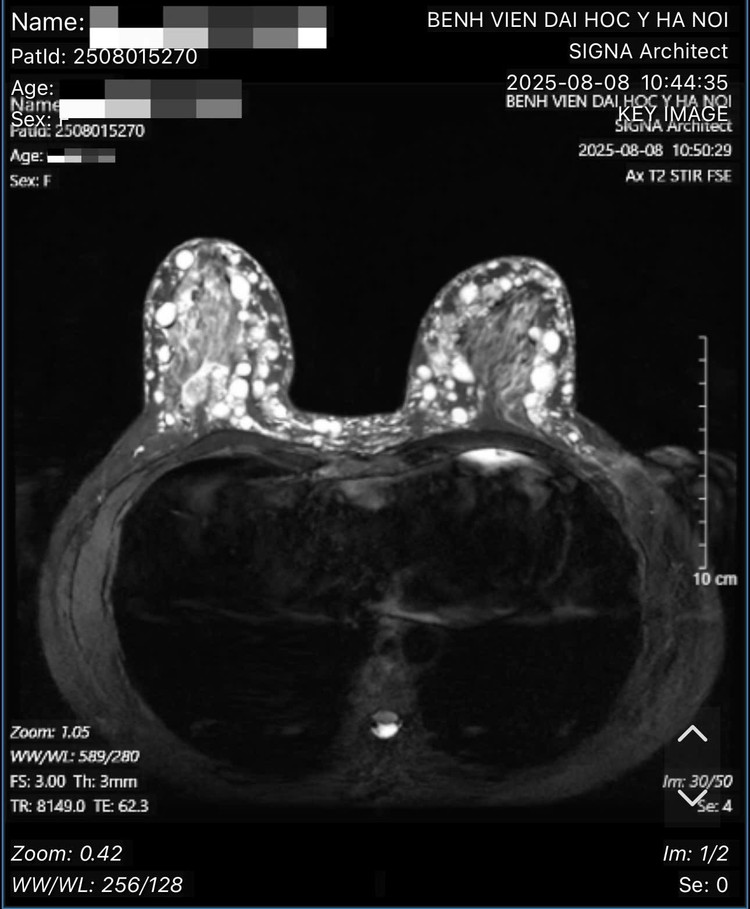

Hình ảnh các hạt sillicone tại ngực bệnh nhân. Ảnh BSCC/Nguồn daibieunhandan.vn

Theo bác sĩ Hồng, qua thăm khám, xét nghiệm và các hình ảnh chụp chiếu, bác sĩ xác định bệnh nhân bị u hạt silicon hai bên ngực (hay còn gọi là siliconoma), thâm nhiễm toàn bộ tổ chức tuyến vú hai bên, đến các tổ chức mỡ dưới da, trung bì da, hay sâu đến lớp cân cơ ngực lớn - là biến chứng của việc tiêm silicon lỏng.